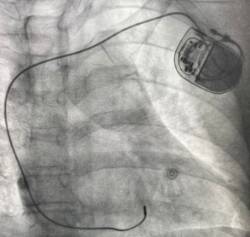

Imagen en alta resolución. Este enlace se abrirá mediante lightbox, puede haber un cambio de contextoUn marcapasos es un pequeño dispositivo que se implanta en el pecho para ayudar a controlar los latidos del corazón. El problema de los marcapasos convencionales es que generan un latido "anormal" o menos fisiológico. Esto hace que algunos pacientes -los que precisan un alto porcentaje de estimulación y sufren algún tipo de cardiopatía- puedan desarrollar complicaciones a largo plazo como hacer que el corazón bombee menos fuerte y en consecuencia retenga líquidos. Afortunadamente, el Hospital La Luz es uno de los centros de España que ofrecen una técnica de implante de marcapasos capaz de prevenir esta clase de problemas.

De acuerdo con el especialista, esta nueva técnica de estimulación puede evitar estas potenciales complicaciones "al colocar el cable en el septo interventricular (la pared que separa el ventrículo derecho del izquierdo) y más concretamente, estimulando la rama izquierda, que es por donde discurre el estímulo cardiaco normalmente, conseguimos un latido lo más parecido al normal y fisiológico".